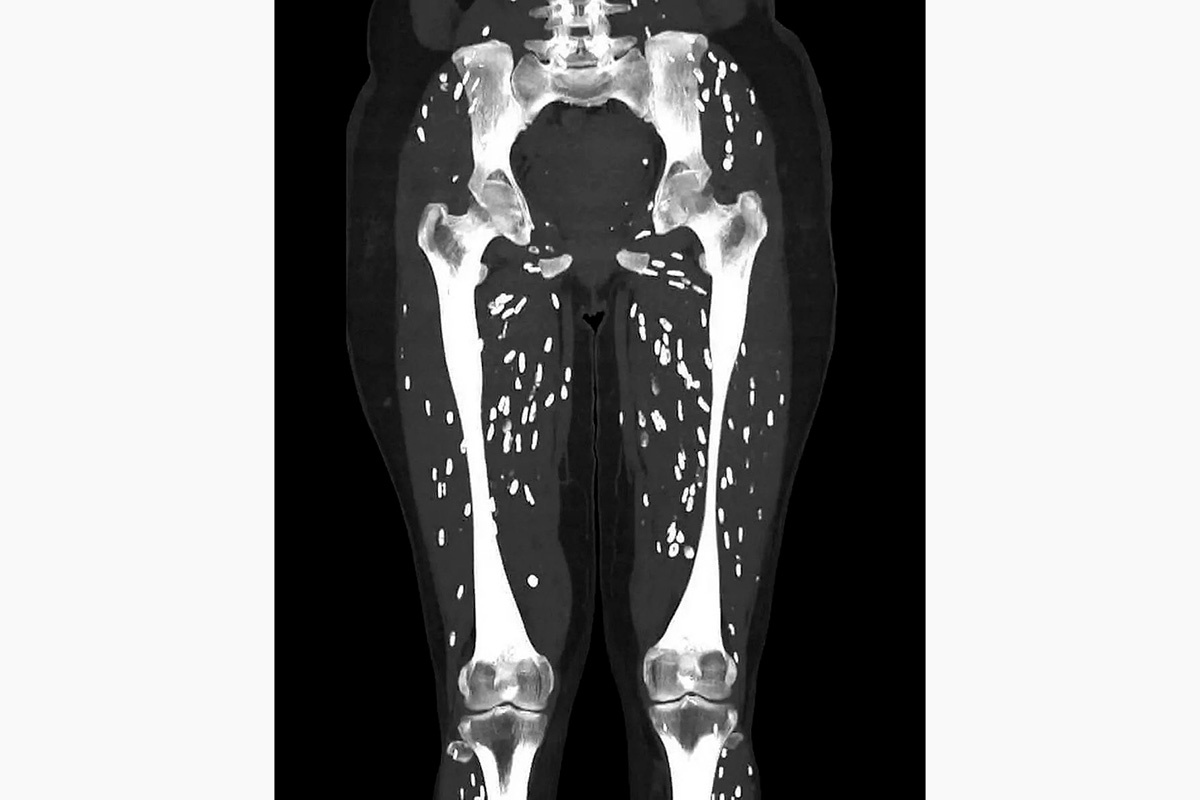

Врач скорой помощи по имени Сэм Гали опубликовал в соцсети X снимки компьютерной томографии, на которых видны последствия употребления полусырой свинины для организма человека. На снимках ясно просматривается, как паразиты поражают мышцы ног пациента.

Инфекция, вызванная паразитом Taenia solium (свиной цепень), приводит к заболеванию, называемому цистицеркозом. Врач пояснил, что заражение происходит, когда человек проглатывает цисты паразита, которые могут находиться в не до конца прожаренной свинине. Попав в организм, личинки проникают в кровоток и распространяются по всему телу, формируя кальцинированные кисты в мышцах или мозге. Эти кисты могут быть ощутимы как небольшие комочки под кожей и хорошо видны на рентгеновских снимках.

EM_RESUS / X📷Снимок с последствиями употребления полусырой свинины для организма человека

Несмотря на то что заражение цистицеркозом может показаться пугающим, врач отметил, что в большинстве случаев воспалительная реакция организма уничтожает кисты. Однако он подчеркнул, что серьезные проблемы могут возникнуть, если паразиты достигают мозга — тогда возникает нейроцистицеркоз. Это заболевание может вызывать головные боли, судороги и другие неврологические симптомы.